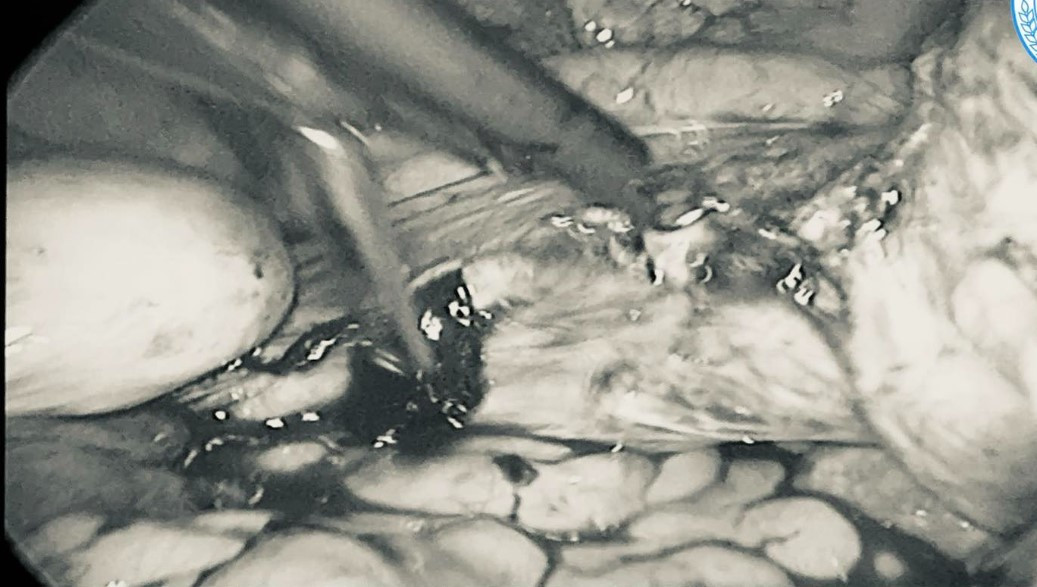

Trong quá trình phẫu thuật, các bác sĩ ghi nhận nhiều khối u xơ lớn trên bề mặt tử cung. Ê-kíp phẫu thuật đã tiến hành xử trí cẩn trọng, bóc tách các khối u xơ bằng phương pháp nội soi.

Hình ảnh khối u kích thước lớn qua nội soi - Ảnh BVCC